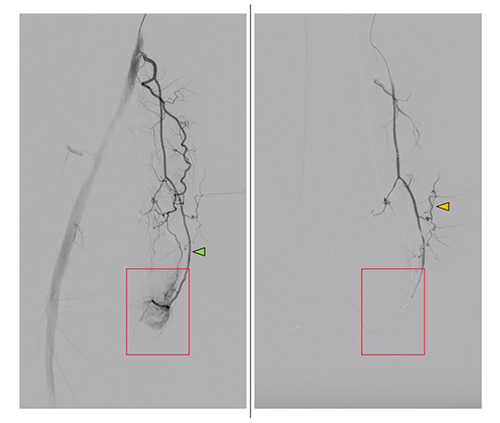

Angiograms of the right knee in a 76-year-old man with knee osteoarthritis. A) Before embolization, selective angiography of the common trunk of the superior lateral and superior medial genicular arteries shows hypervascular inflammatory blush (arrows). B) During embolization using ethiodized oil of the common trunk, the angiogram shows emulsion droplets (arrows). Image courtesy of Diagnostic and Interventional Imaging.